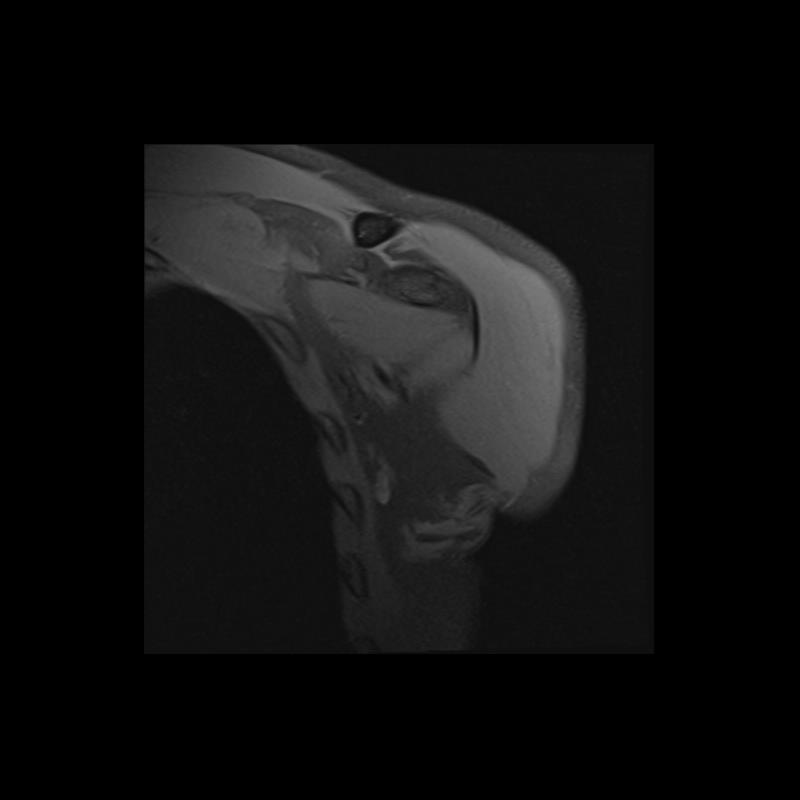

Shoulder MRI Anatomy